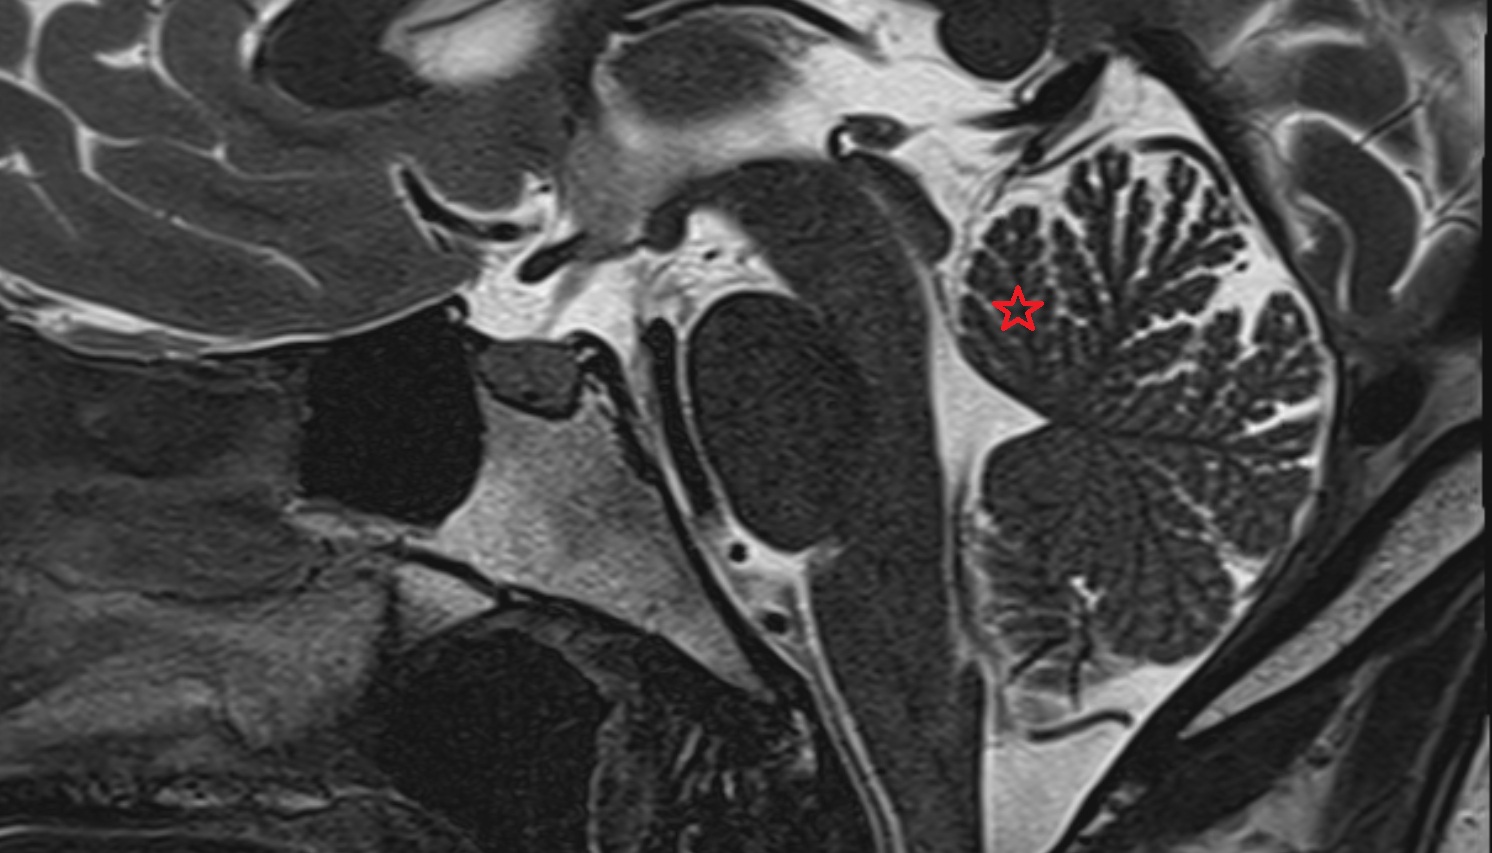

- Arbor Vitae (Cerebellar White Matter)

- Cerebellum

- White matter of cerebellum (Arbor vitae)